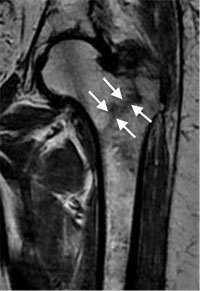

In some cases, if the patient falls and complains of hip pain, an incomplete fracture may not be seen on a regular X-ray. In that case, magnetic resonance imaging (MRI) may be recommended. The MRI scan will usually show a hidden fracture.

An MRI may identify a hip fracture otherwise missed on plain X-ray.